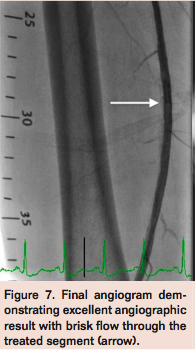

Access was obtained in the left common femoral artery (CFA) and a 7 Fr Pinnacle Destination sheath (Terumo) was positioned across the aortic bifurcation in the right CFA. Selective angiogram of the right lower extremity confirmed mid to distal 80% calcified stenosis of the right SFA (Figure 1), mild popliteal artery disease, and 2-vessel run-off into the right foot. A Grand Slam Wire (Abbott Vascular) was advanced across the right SFA lesion into the distal peroneal artery after anticoagulation with intravenous heparin. Intravascular ultrasound (IVUS) imaging (Volcano) was performed to determine the burden and character of the plaque, which confirmed a severe calcific and eccentric stenosis in the mid SFA (Figure 2). Rotational atherectomy with aspiration thrombectomy was performed using a Jetstream 2.1/3.0 atherectomy catheter (Bayer HealthCare) with four passes across the lesion, two with blades down and two with blades up (Figure 3). Follow-up angiography displayed improved flow but with a non-flow-limiting dissection within the treated segment of the right SFA (Figure 4). Repeat IVUS imaging confirmed an intimal flap consistent with post-atherectomy dissection (Figure 5). Nitinol-constrained balloon angioplasty was performed using a 5 mm x 80 mm over-the-wire Chocolate PTA balloon catheter (TriReme Medical) with a prolonged expansion over 2 minutes (Figure 6). Final angiogram demonstrated excellent angiographic result with brisk flow through the treated segment (Figure 7) and preserved run-off into the foot. Final IVUS imaging confirmed no residual dissection flap and improved luminal gain (Figure 8).